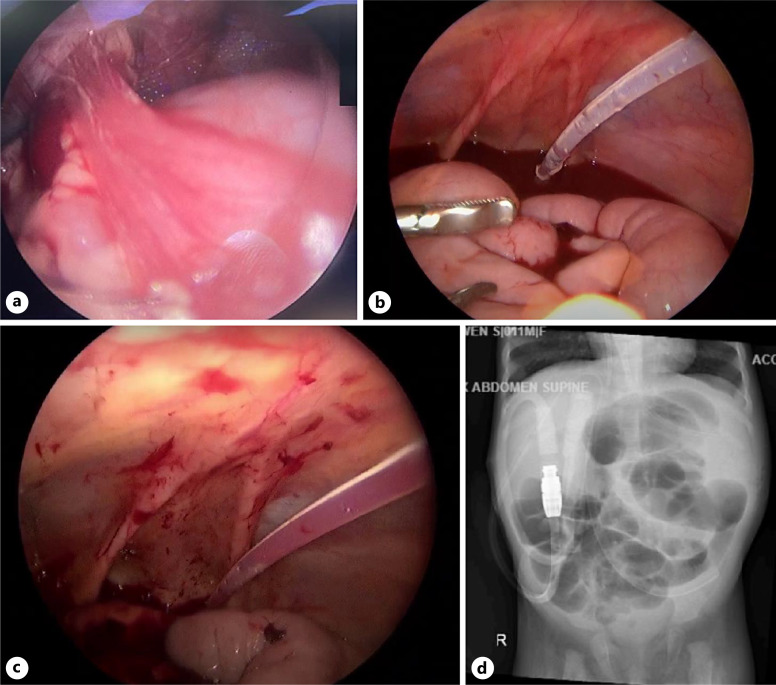

Case presentation: We reported a case of PD catheter adhesion to the ileum in a 1-year-old girl. Previously, the patient underwent laparoscopic insertion of PD catheter due to ESKD. One month after the procedure, there were signs of catheter obstruction. Laparoscopy evaluation and revision were carried out.